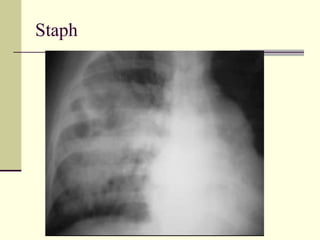

Cavitating Pneumonia   1. Staph  2. Strep 3. TB  4. Gram negative (Klebsiella)

Staph